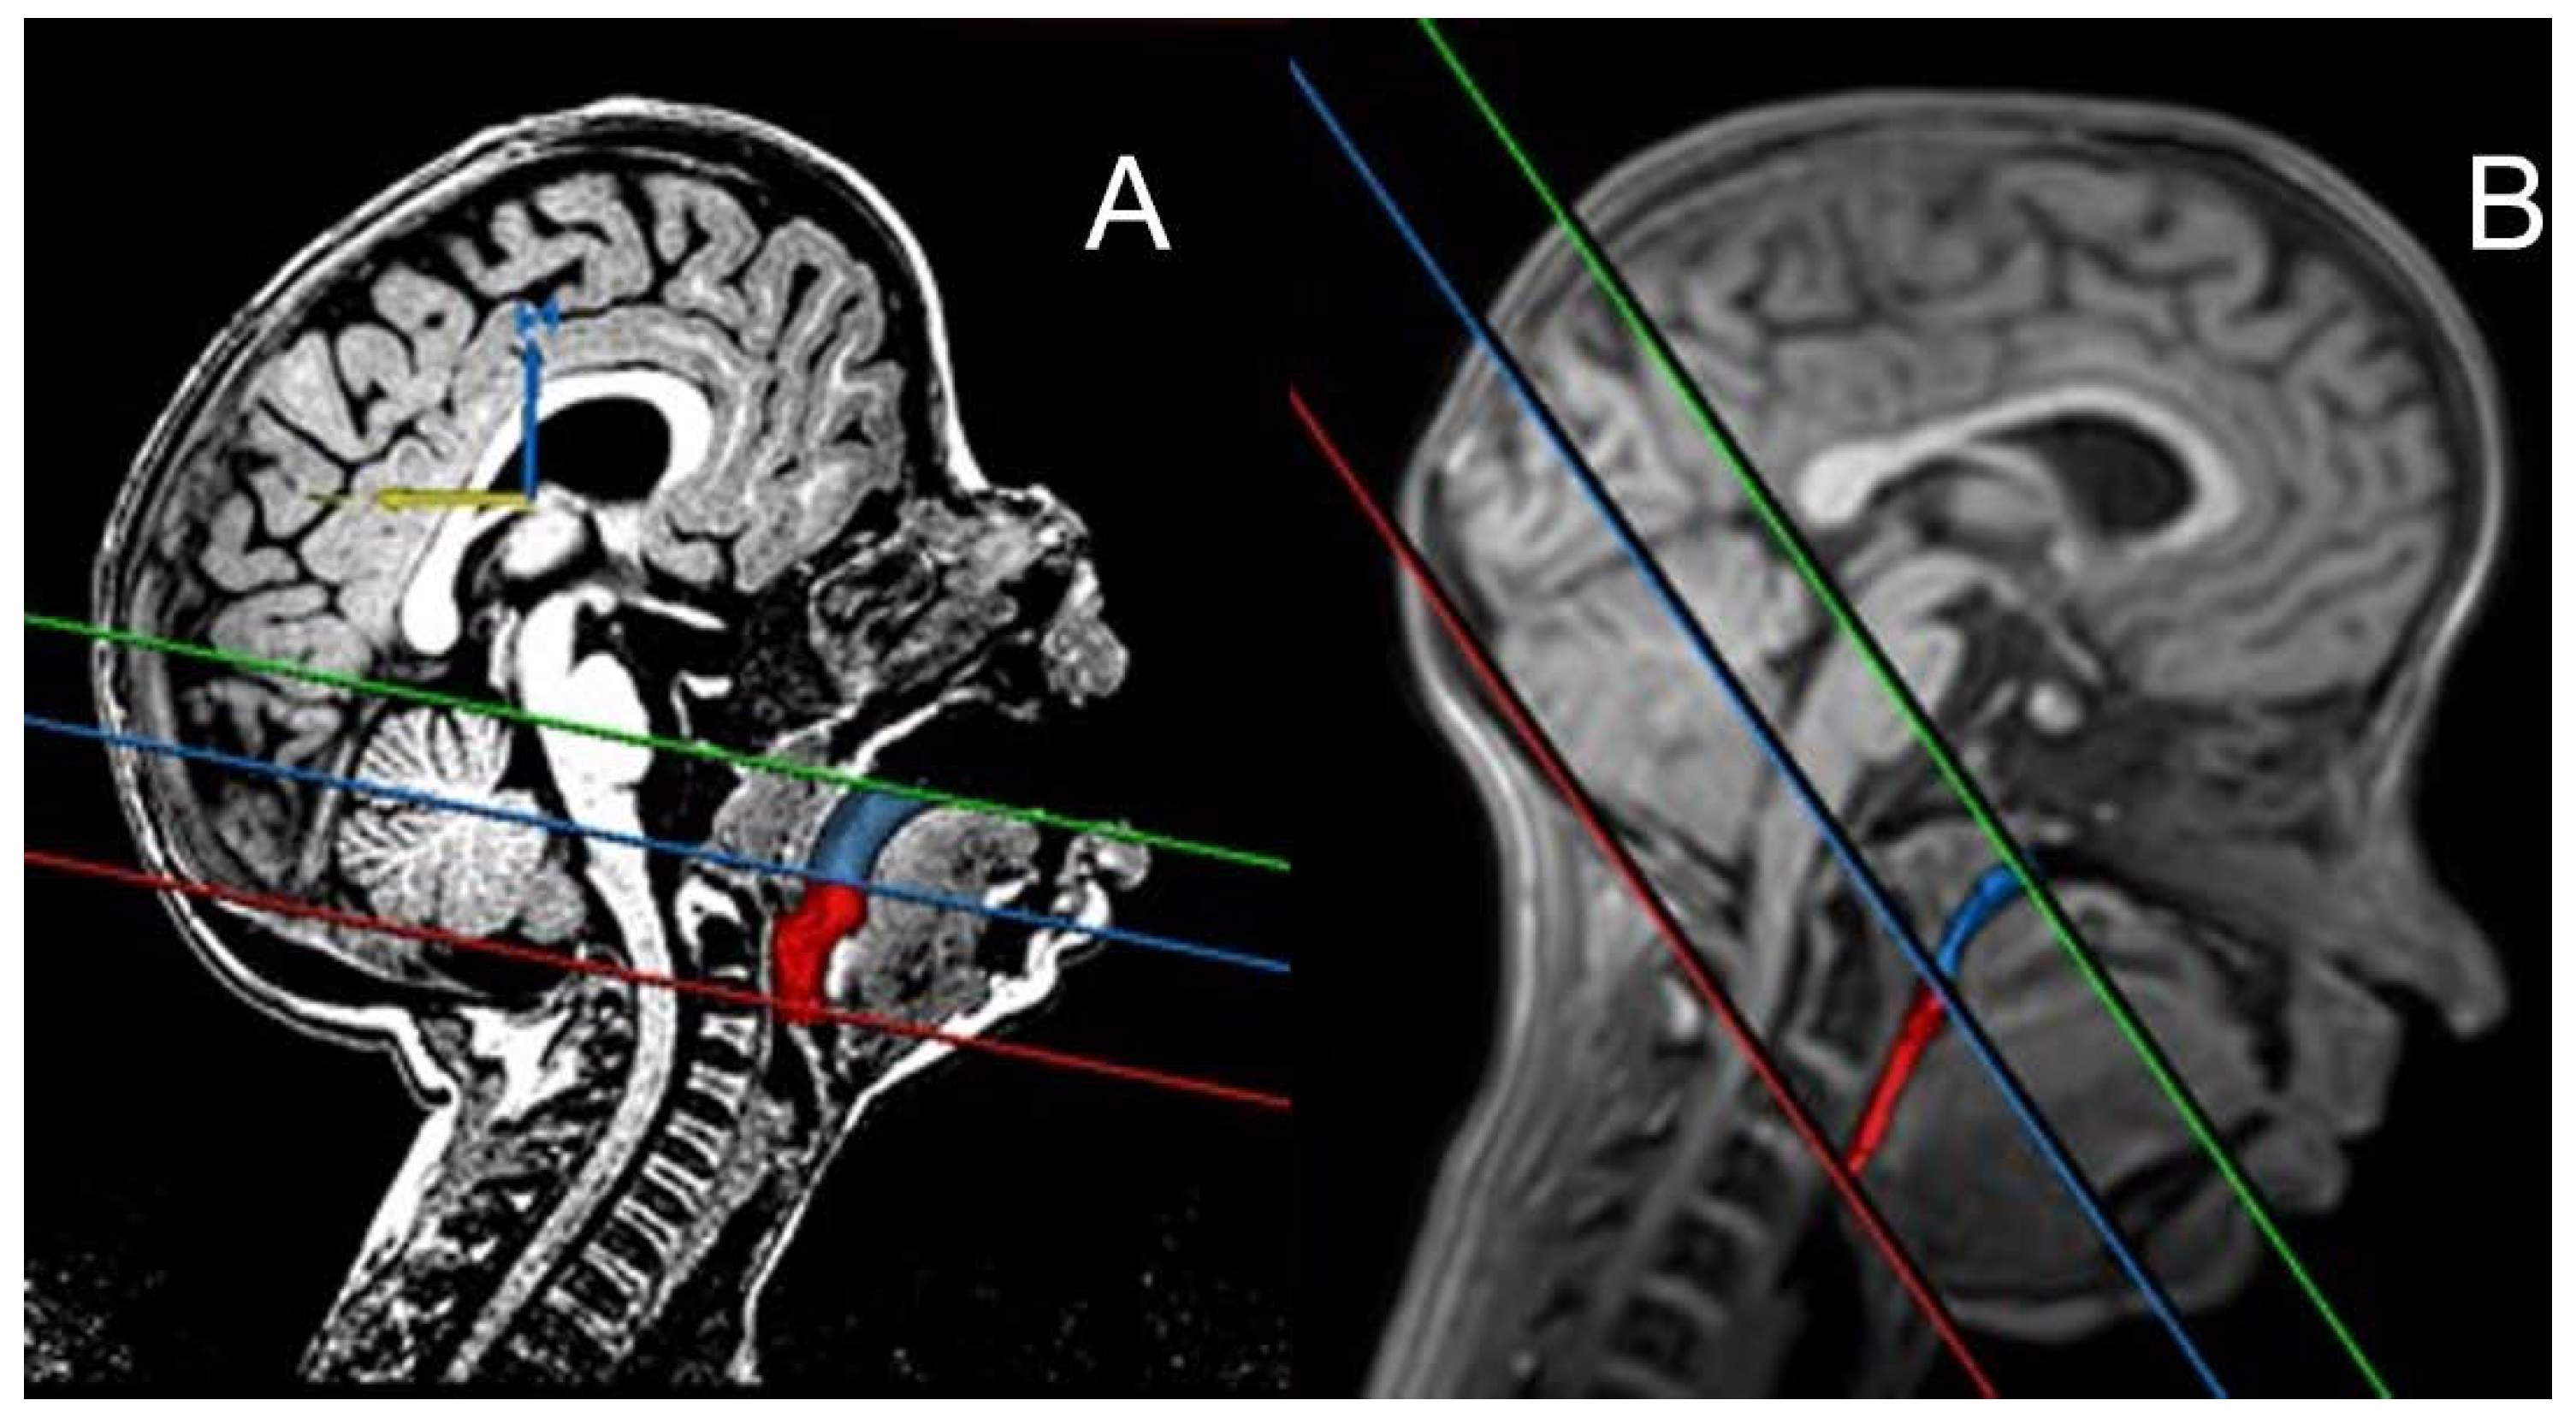

2.7. Quantitative Point-Based Assessment of Airway: PAS, MPH, Radius, and Perimeter

3.3. Quantitative Point-Based Assessment of Airway

- Imaging Variability: The pre-orthodontic lateral cephalogram (T2) was performed with the patient’s mouth open. Consequently, the cephalometric analysis focused on dental changes, particularly the inclination of the incisors. A significant limitation of this study is the lack of a reliable quantitative assessment of upper airway volume due to differing patient head positions during the pre- and post-treatment NMR scans. The patient was anesthetized for anxiolysis during the N0 scan, which was taken in a supine, open-mouth position. In contrast, the N1 examination was performed in a supine, closed-mouth position while the patient was awake. Therefore, the upper airway anatomy could not be accurately compared between the NMR scans taken before and after UPP, due to potentially confounding imaging biases [26,27].